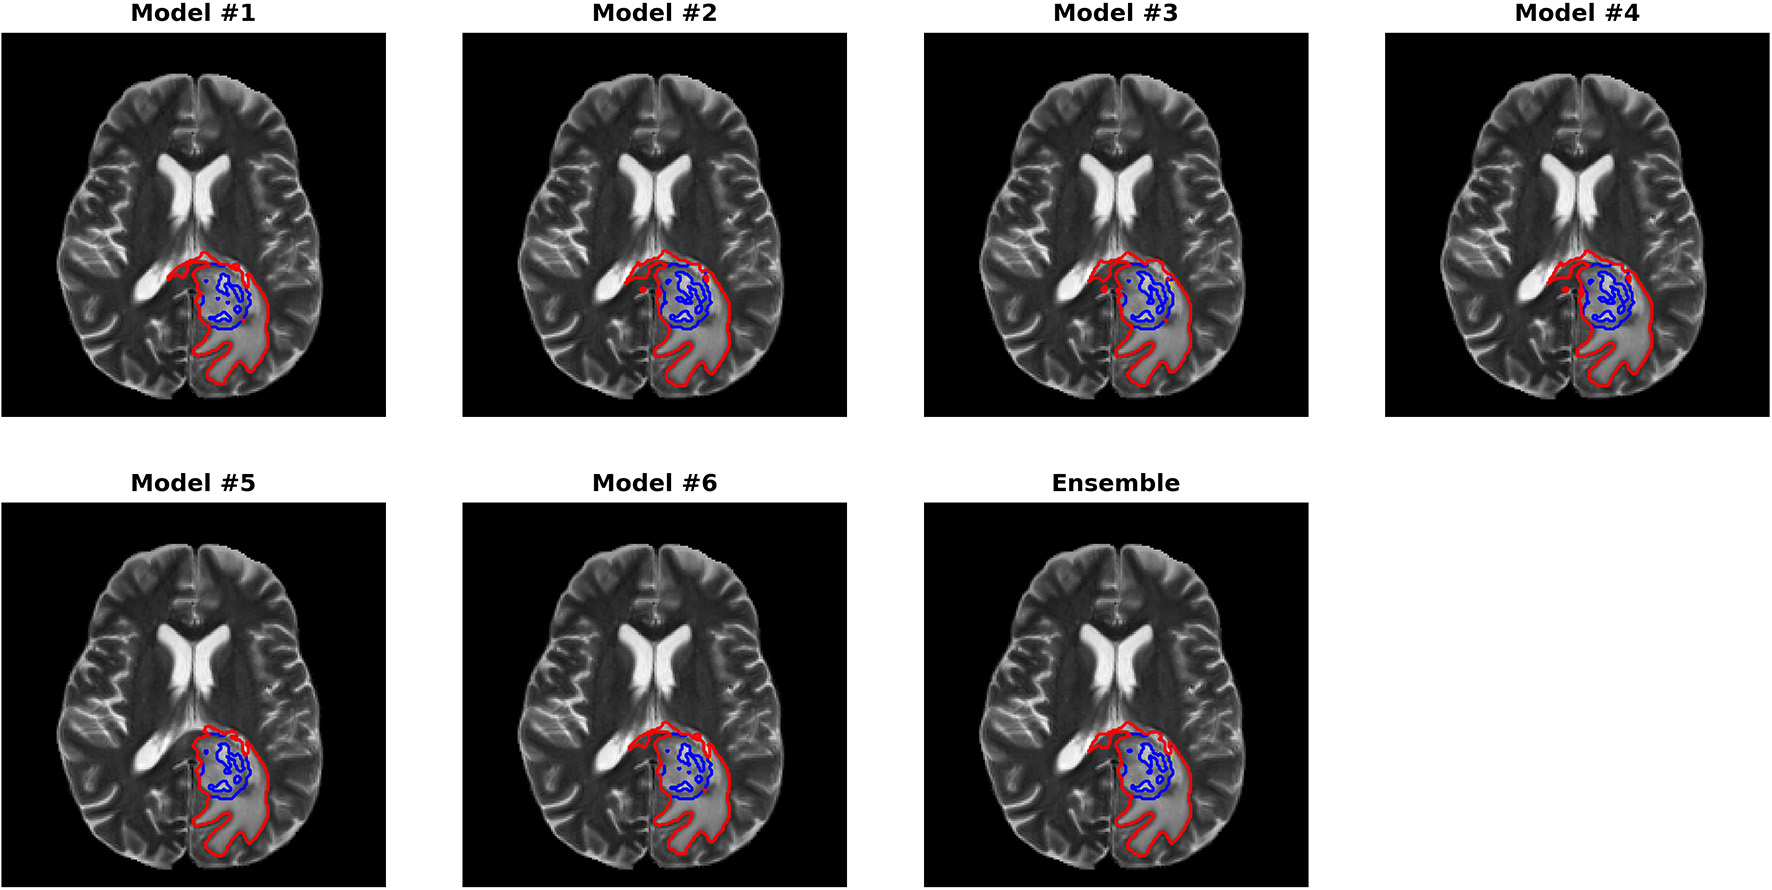

Figures 3, 4 show two slices (axial slice 76 and 81) of the automatically segmented labels overlaid on the T1Gd and T2 images, respectively. The showed case was “Brats18_CBICA_BHF_1” and was randomly selected from the validation dataset for demonstration. A single model may suffer from under- or over-segmentation while the average of multiple models achieves a more stable performance, which is also closer to the ground-truth, as shown with the improved Dice scores. Furthermore, the ensemble of all 6 models yields a much smoother boundary for different sub-regions and eliminates a few isolated regions, which are likely false positives.

FIGURE 3

www.frontiersin.org

Figure 3. Automatically segmented sub-regions from models 1–6 and the ensemble model. The underlying image is the corresponding T1Gd from the validation case “Brats18_CBICA_BHF_1.” Red, yellow and blue delineate the predicted boundaries of the total tumor, enhanced tumor core, and peritumoral edema, respectively.

Figure 4. Automatically segmented sub-regions from model 1–6 and the ensembled model. The underlying image is the corresponding T2 from the validation case “Brats18_CBICA_BHF_1.” Red, yellow and blue delineate the predicted boundaries of the total tumor, enhanced tumor core, and peritumoral edema, respectively.